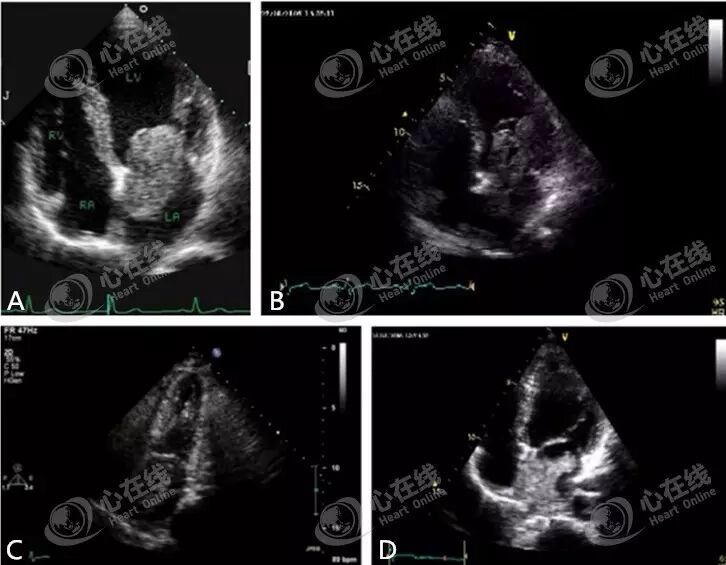

观察四心腔切面(图A)、两心腔切面(图B)、三心腔切面(图C),可见左室心梗后形成的各类型血栓,且均附着在左室心尖部。

图A显示右室的十字形占位性病变,观察可见右室房室环部位出现肿块,且右心明显扩大。观察图B可见左室外侧有一个瘤腔,且左室壁连续中断,彩色多普勒可见贯通于左室腔和瘤体之间的血流信号,提示假性室壁瘤。